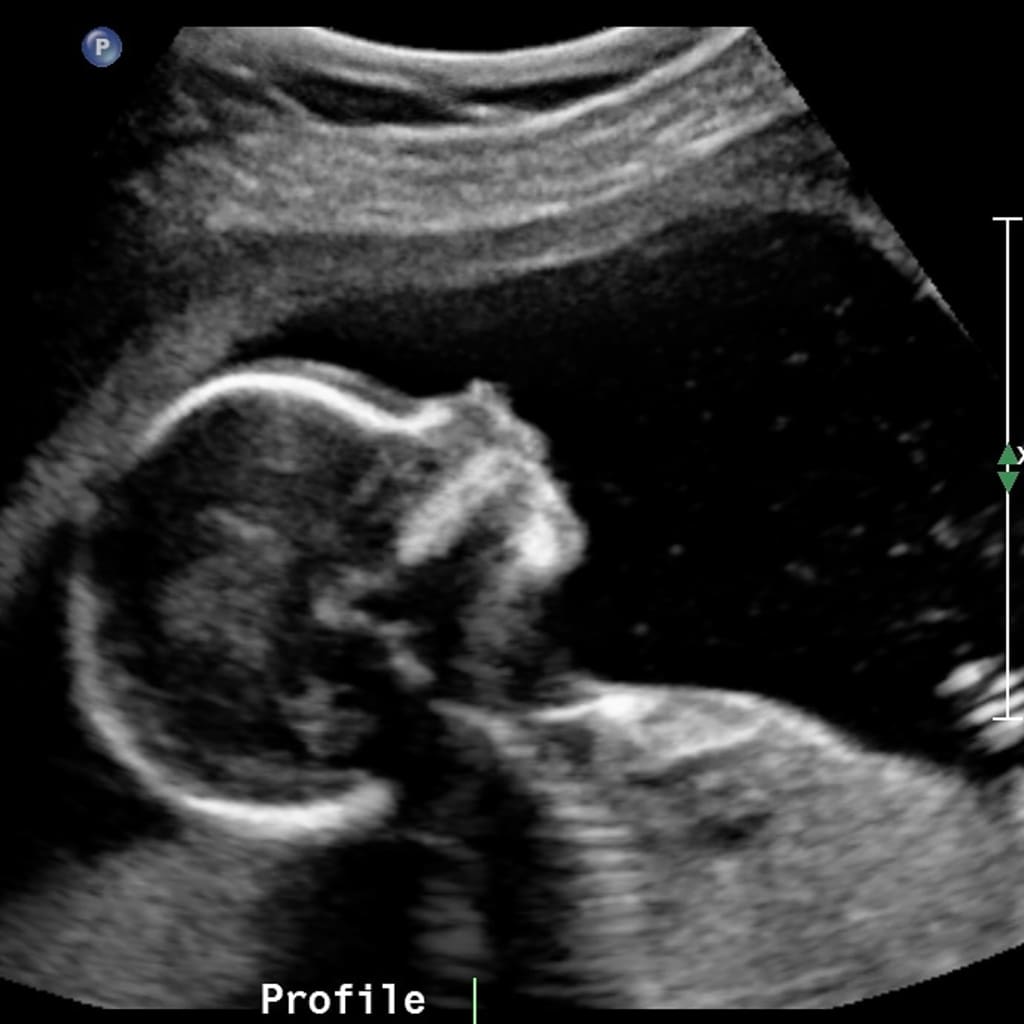

The day I found out I was pregnant was the day my life would change forever, as most would expect me to say. How my life changed, is a whole different story. I was single at the time, and still am. I was currently working at a local restaurant as a waitress, and the hours varied from week to week, most being late at night. I took my 3 positive tests in the end of May, and summer was just getting started. The restaurant was getting busier and busier while my stomach was getting sicker and sicker. It didn’t help that parts of the restaurant didn’t have working air conditioning, like the kitchen where it was needed most. My blood pressure dropped and tended to stay low due to the pregnancy, and I got light-headed very easily. This plus the extra heat of the summer at work didn’t make for a good combination. I cut back on hours to help get rested for the days I did have to go in, but even that wasn’t enough to get through my shifts. I ended up quitting but didn’t have anything lined up which rendered me unemployed as of mid-July. Even though I had some money saved, the worry started to set in real fast.

Let me lay out some of these details in a simpler way without all the extra stuff. Throughout the first six months of my pregnancy, the first two trimesters, I have been employed for about three to three and a half of those months, and been declared unemployed twice. Not to mention, I have no man with a second income to rely on. Am I saying all this to complain? No. Am I saying all this to ask for someone’s pity? Hell no. I’m about to show you all that I’ve accomplished in those six months, and all I’ve been able to do for my son regardless of my situation. Then, I’m gonna tell you that you can do it too and tell you how!